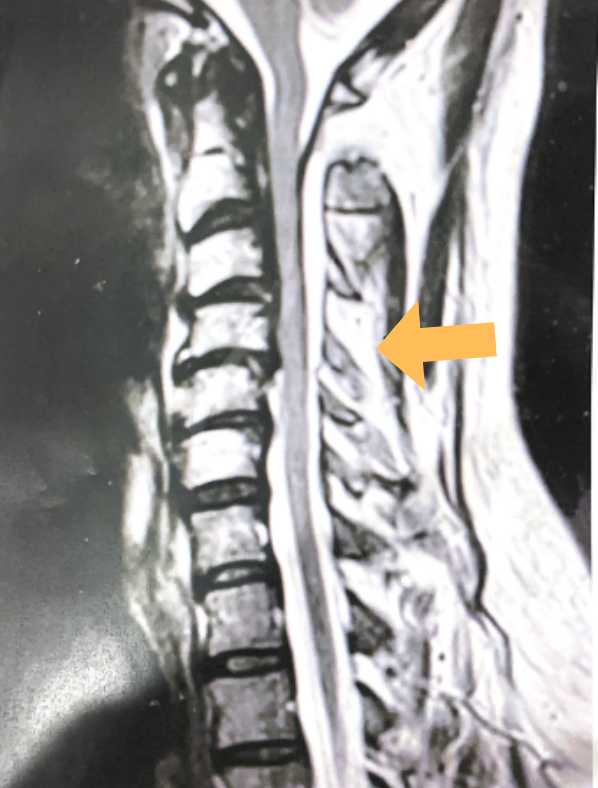

Spine:

Thoracic Spinal Cord Tumor Case Presentation

Author: Xavier P. J. Gaudin D.O., F.A.C.O.S., Read More!